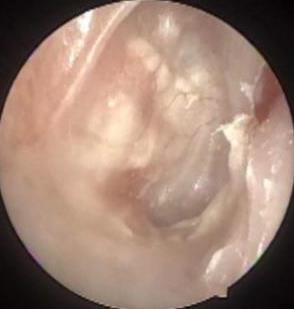

摘要:目的 分析医用生物蛋白胶应用于耳内镜下鼓膜修补术的临床疗效。方法 回顾性分析2022年10月-2023年10月该院收治的60例单纯鼓膜穿孔患者的临床资料,根据手术方法不同,将患者分为研究组和对照组,各30例。研究组术中使用医用生物蛋白胶粘合残余鼓膜和修补材料;对照组术中采用明胶海绵覆盖修补鼓膜。观察两组患者术后的鼓膜愈合情况(鼓膜愈合率、愈合时间、干耳时间和外耳道上下径)和并发症发生情况;于手术前后,采用纯音测听法(500、1 000、2 000、4 000 Hz),测量两组患者气导阈值,观察听力改善程度;采用视觉模拟评分法(VAS)评分,评估患者术后疼痛程度。结果 两组患者术后鼓膜愈合率、愈合时间、外耳道上下径和并发症发生率比较,差异均无统计学意义(P > 0.05)。研究组术后平均气导听阈明显低于对照组,差异有统计学意义(P < 0.05)。研究组术后干耳时间短于对照组,术后第1天疼痛VAS评分明显低于对照组,差异均有统计学意义(P < 0.05)。结论 医用生物蛋白胶应用于耳内镜下鼓膜修补术,可有效地降低气导听阈,缩短干耳时间,减轻患者疼痛,且不增加并发症发生率,值得临床推广应用。